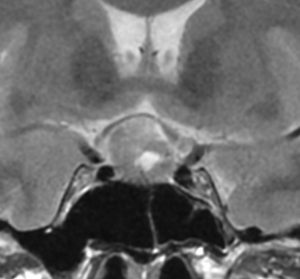

40代の女性に,軽度の両耳側半盲で発生したものです。視交叉と視床下部の下面に腫瘍があり,下垂体柄の位置が全くわからず,下垂体の前葉と後葉は侵されていません。ですから,下垂体柄から発生した腫瘍であり,pituicytomaが強く疑われます。T2ではほぼ等信号,小さなのう胞があり,ガドリニウムで強く増強されます。手術では正常下垂体柄の一部が右側にうすく残っており,幸運にも亜全摘出できて下垂体機能は温存できました。残存腫瘍は増大傾向を示していません。でも,このようなタイプを積極的に摘出すると,汎下垂体機能低下症を招くことが多いので,手術するかどうかの判断はとても難しいです。